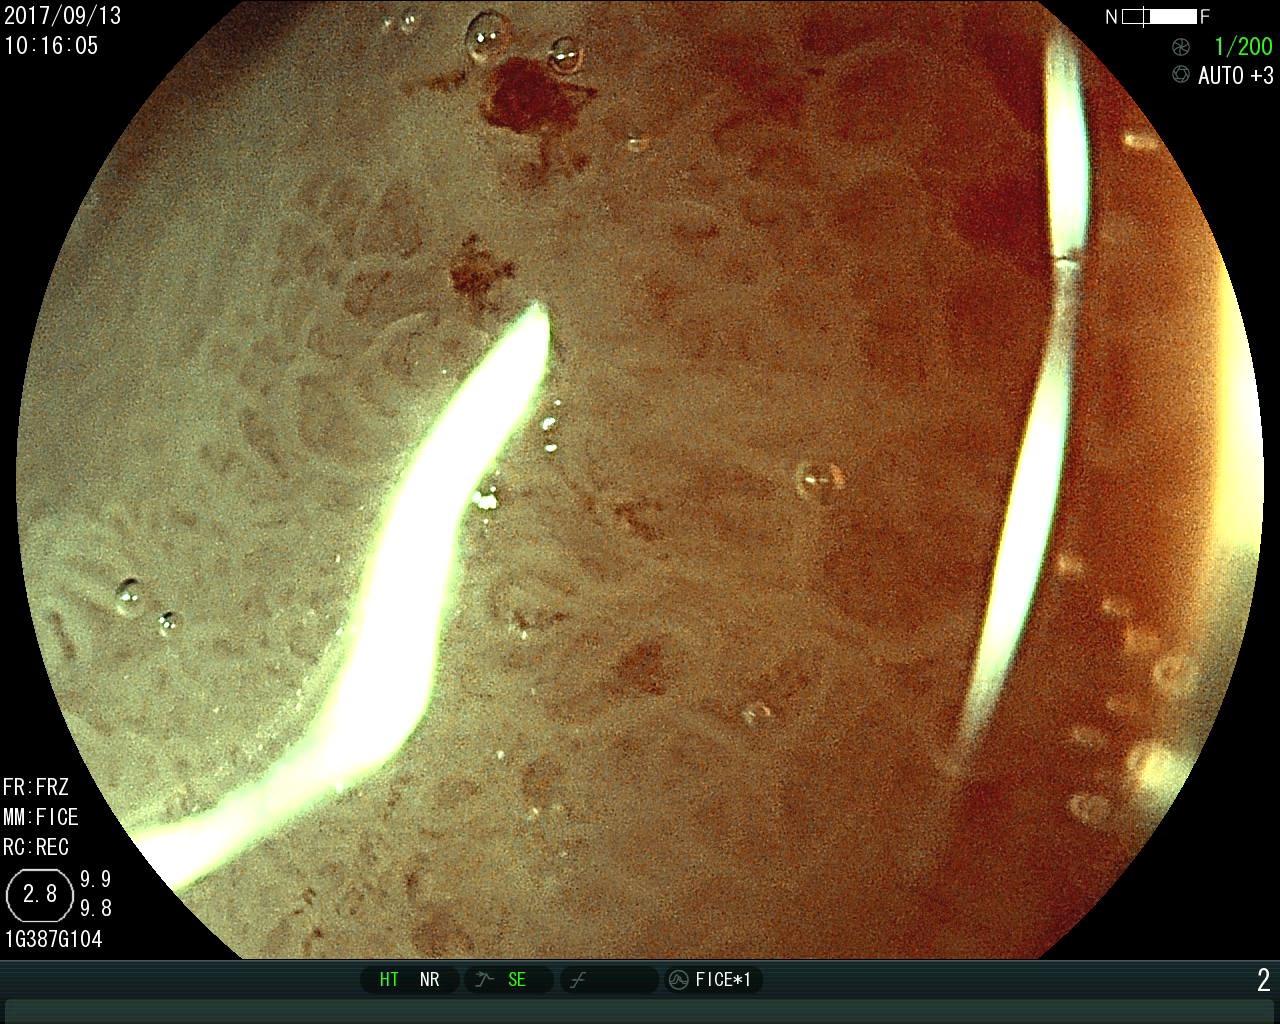

早期胃癌的放大胃镜图片